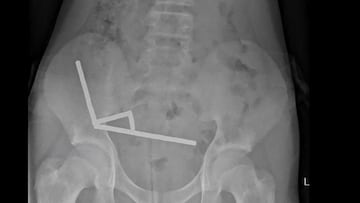

Una radiografía mostró imanes agrupadas en cuatro líneas rectas dentro de los intestinos del niño “Parecían estar en partes separadas del intestino, adheridas entre sí debido a fuerzas magnéticas”, dijeron.

Los imanes, que están prohibidos en Nueva Zelanda desde enero de 2013, fueron comprados en una plataforma de compras en línea (Temu dijeron las autoridades). Cuando el niño pasó por la zona de rayos X, la radiografía mostró que los imanes se habían agrupado en cuatro líneas rectas dentro de los intestinos del niño. “Estas parecían estar en partes separadas del intestino, adheridas entre sí debido a fuerzas magnéticas”, dijeron, mostrando la imagen que aparece en esta noticia.